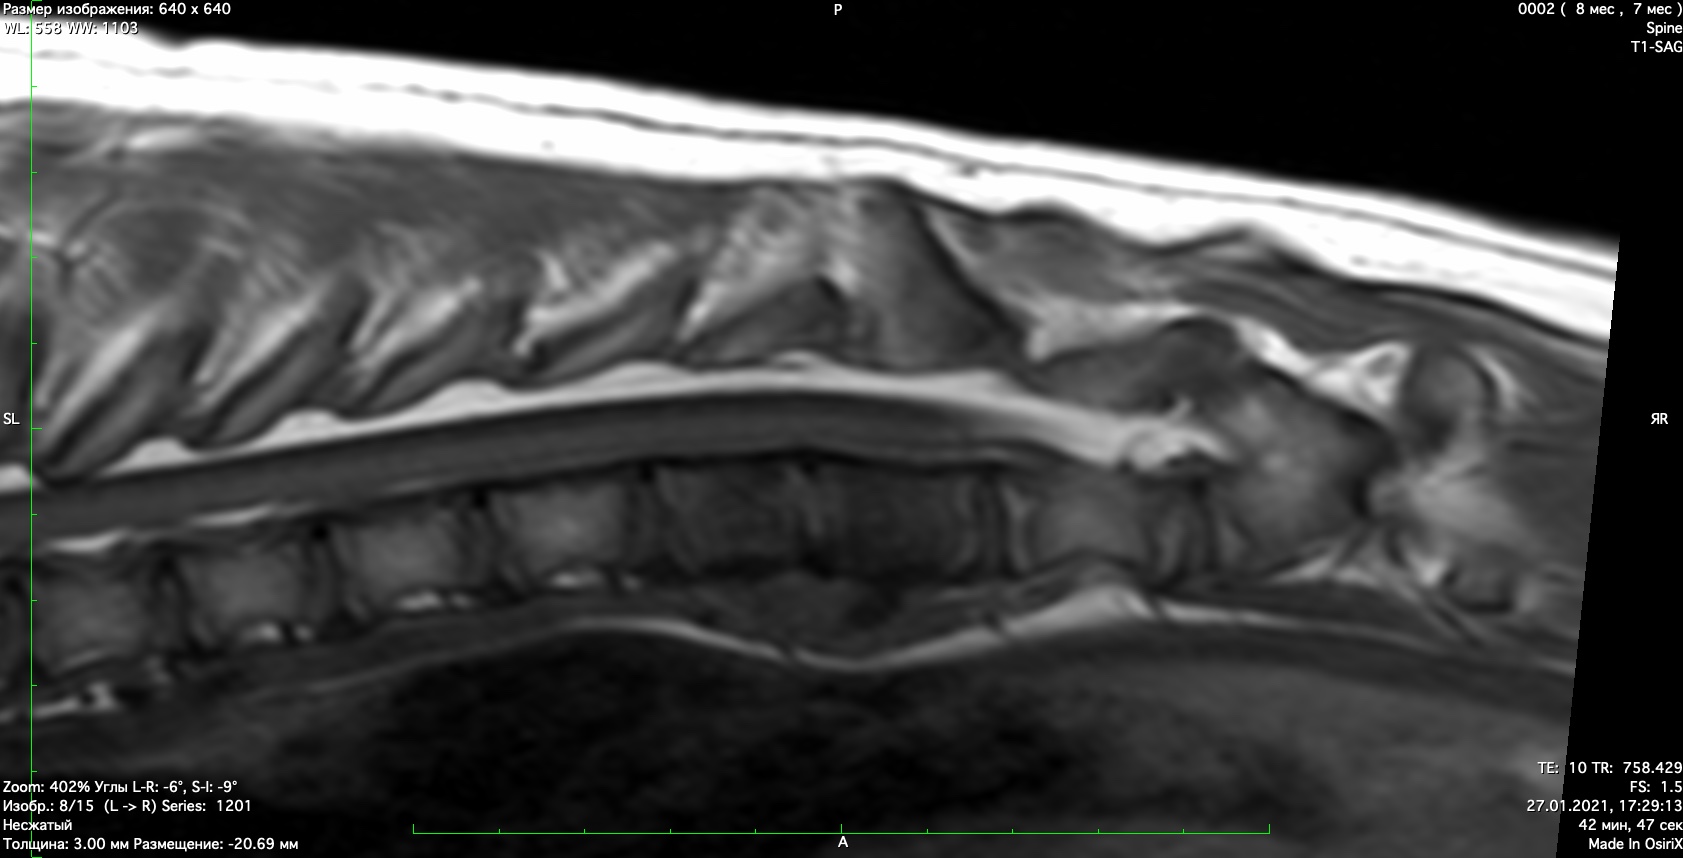

При проведении неврологического осмотра установлено- неврологический дефицит отсутствует, сильная болезненность при пальпации поясничного отдела позвоночника При проведении мрт диагностики установлено признаки воспаления позвонков поставлен диагноз-дискоспондиллит. начато лечение дискоспондиллита -антибиотиками